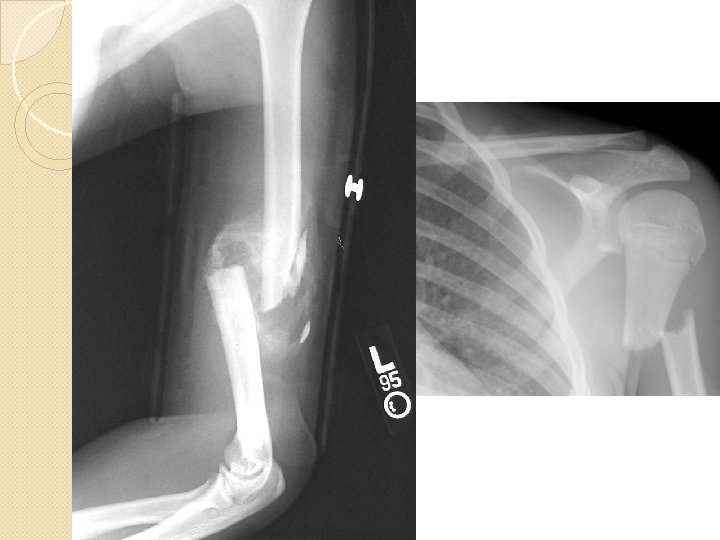

�Humeral Fx: ◦ Musculature can hide fx to humeral head ◦ Sprains can often mimic fx ◦ MOI: Direct blow (most common), falling on elbow (axial load), overuse (least common) ◦ Tx: cast, ORIF (if necessary), modify activity (stress fx)

�Epiphyseal Injuries ◦ Injury to growth plate ◦ MOI: Direct blow, falling on elbow, overuse (most common) ◦ Can cause permanent growth impairment �Avulsion Fx: ◦ Lig/tendon pulls away from bone ◦ Most commonly occurs during shoulder dislocation

�Dislocation/Subluxation ◦ MOI: excessive abduction and external rotation ◦ Shoulder appears flat ◦ May be assoc fx or labral tear, must f/u with Ortho �Multiple disloc occur, surgery may be necessary